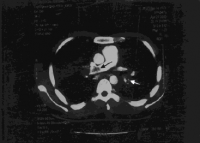

- טומוגרפיה ממוחשבת CT Angio (Copmuter Tomography) –הבדיקה מאפשרת להביט על גודלם של עורקי הריאה ועוזרת לאשר או לשלול מחלות ריאה אחרות היכולות לגרום ליתר לחץ דם ריאתי כמו קרישי דם בעורקי הריאה